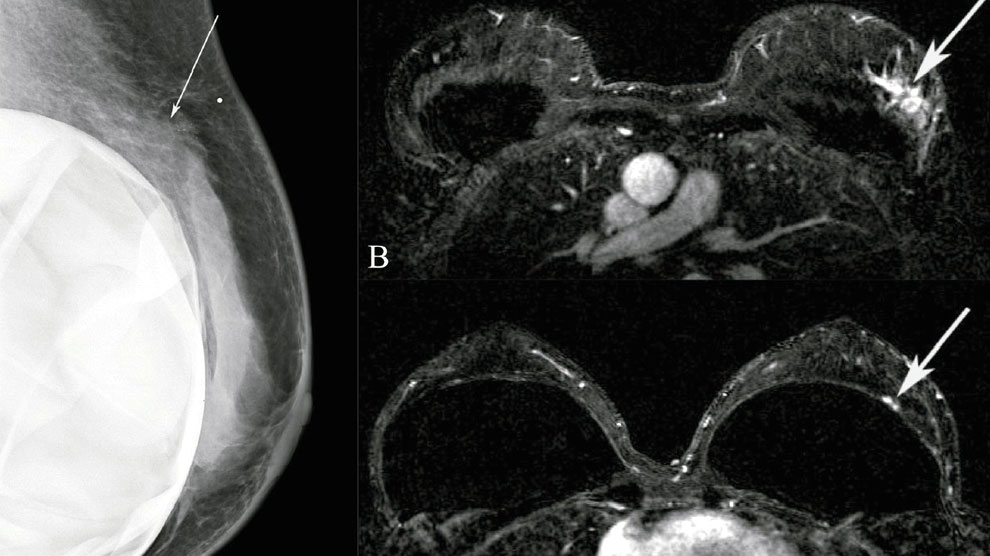

Ilustrasi: foto payudara (sumber: ijri.org)